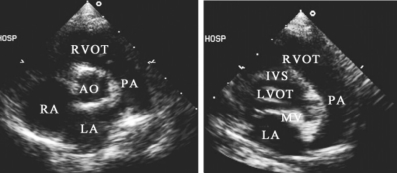

1.14.2.2二、常用切面图及用途

-